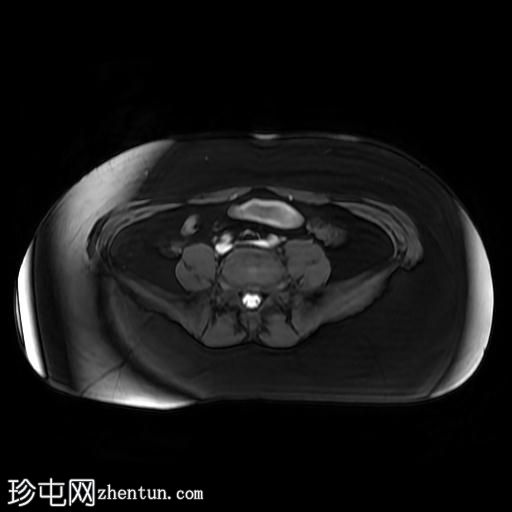

4.jpeg

轴位T1

脂肪饱和度

MRI序列显示:

女性外生殖器

子宫、宫颈及阴道上2/3缺失

左侧睾丸及腹股沟管内环

右侧睾丸位于腹腔内,靠近腰大肌

双侧卵巢未显影

MRI结果提示雄激素不敏感综合征 (AIS),患者基因构成为男性,但外生殖器为女性(46XY核型)。由于细胞对睾酮等雄激素产生抵抗,雄激素不敏感综合征常伴有双侧隐睾。

区分雄激素不敏感综合征与Mayer-Rokitansky-Küster-Hauser综合征(MRKH)至关重要。MRKH综合征具有女性核型,女性外生殖器和卵巢正常,但子宫缺失或发育不全。